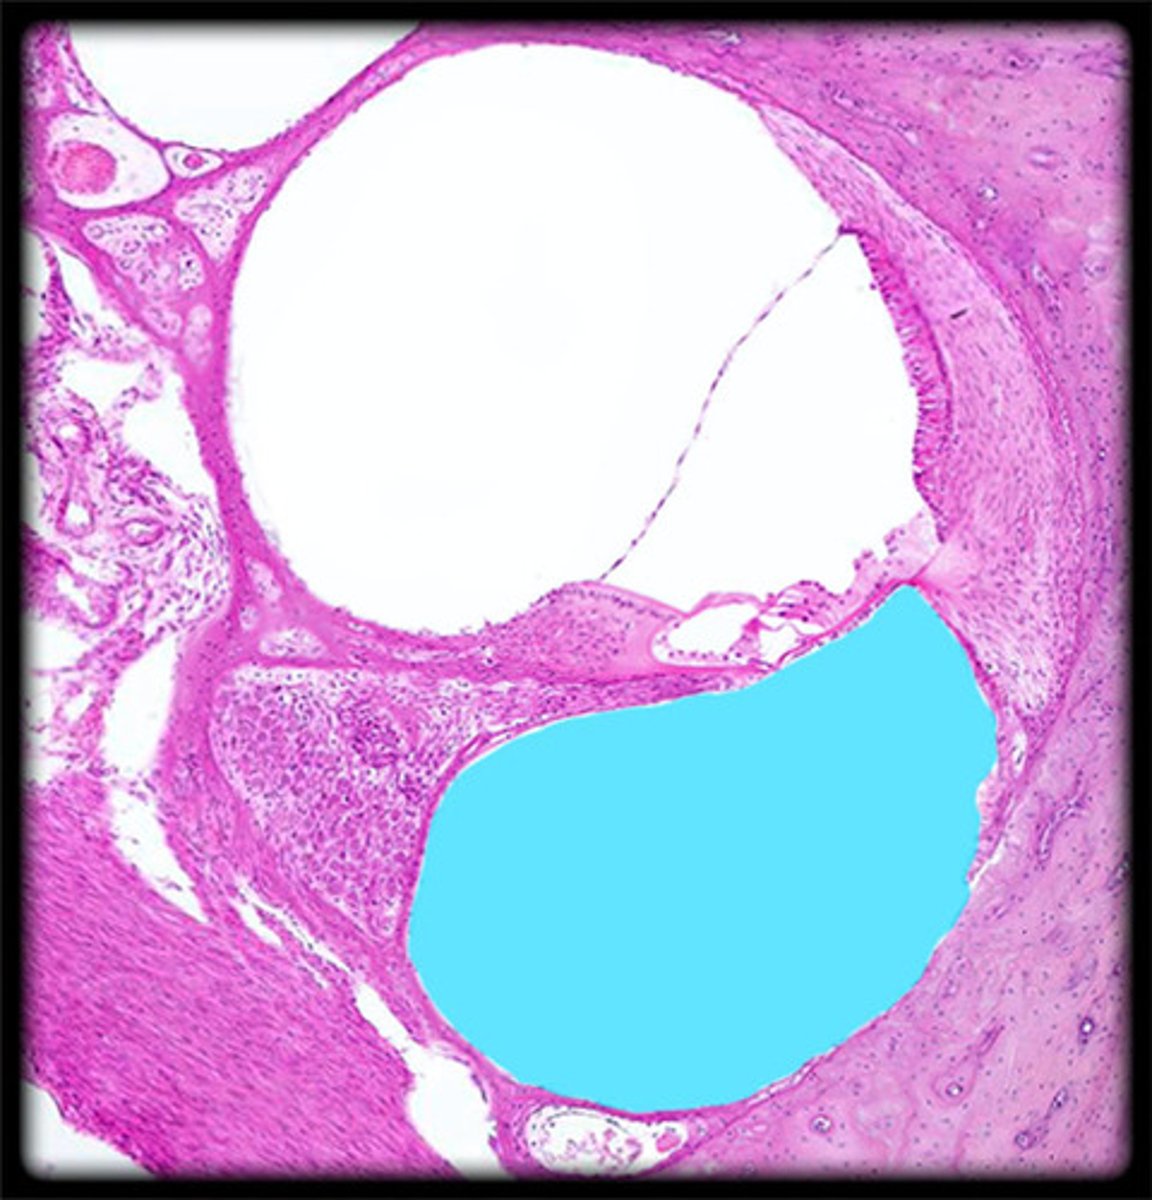

cochlea histology

scala vestibuli

contains perilymph

scala media

contains endolymph

scala tympani

vestibular membrane

organ of Corti

tissue containing the hair cells necessary for hearing

basilar membrane

hair cells

tectorial membrane